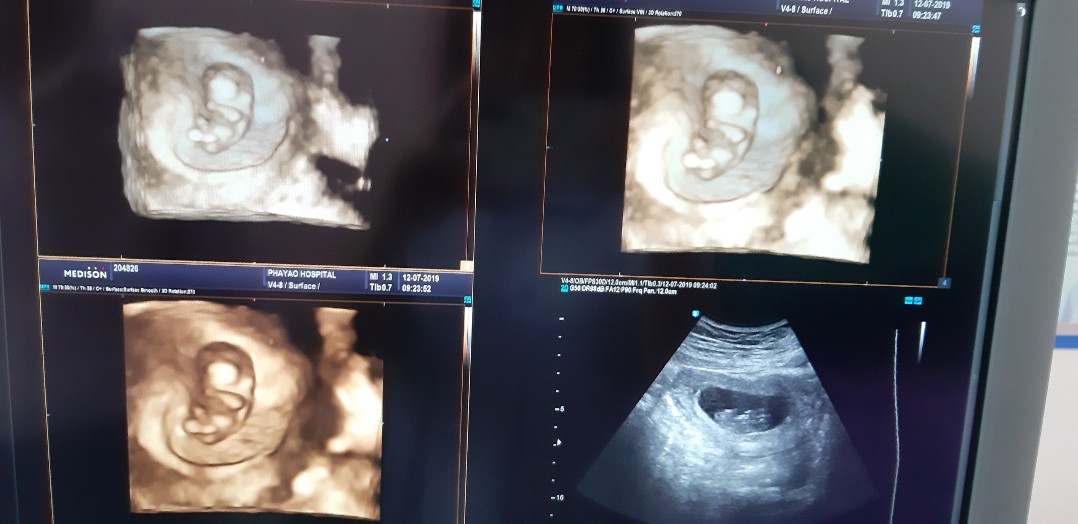

19+1จ้าาา เพศ ญ